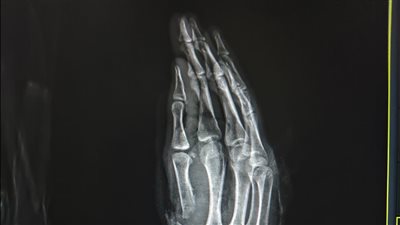

وتناولت الحملة عددًا من المحاور التوعوية المهمة، شملت التعريف بالأعراض المبكرة لمرض السكري وطرق اكتشافه في الوقت المناسب، والحالات التي تستدعي استشارة الطبيب، وأهم مضاعفات المرض وسبل الوقاية منها، إلى جانب توضيح علامات الغيبوبة السكرية وكيفية التعامل معها وتقديم الإسعافات الأولية اللازمة.